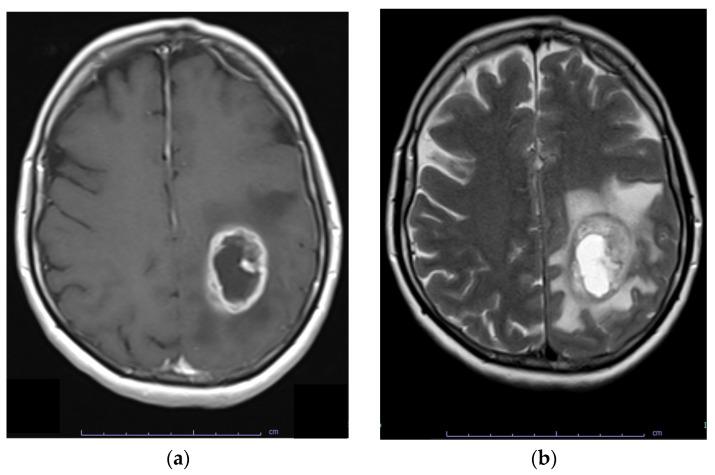

Glioblastoma, the most aggressive and common malignant primary brain tumour, is characterized by infiltrative growth, abundant vascularization, and aggressive clinical evolution. Patients with glioblastoma often face poor prognoses, with a median survival of approximately 15 months. Technological progress and the subsequent improvement in understanding the pathophysiology of these tumours have not translated into significant achievements in therapies or survival outcomes for patients. Progress in molecular profiling has yielded new omics data for a more refined classification of glioblastoma. Several typical genetic and epigenetic alterations in glioblastoma include mutations in genes regulating receptor tyrosine kinase (RTK)/rat sarcoma (RAS)/phosphoinositide 3-kinase (PI3K), p53, and retinoblastoma protein (RB) signalling, as well as mutation of isocitrate dehydrogenase (), methylation of O-methylguanine-DNA methyltransferase (), amplification of epidermal growth factor receptor vIII, and codeletion of 1p/19q. Certain microRNAs, such as miR-10b and miR-21, have also been identified as prognostic biomarkers. Effective treatment options for glioblastoma are limited. Surgery, radiotherapy, and alkylating agent chemotherapy remain the primary pillars of treatment. Only promoter methylation of the gene predicts the benefit from alkylating chemotherapy with temozolomide and it guides the choice of first-line treatment in elderly patients. Several targeted strategies based on tumour-intrinsic dominant signalling pathways and antigenic tumour profiles are under investigation in clinical trials. This review explores the potential genetic and epigenetic biomarkers that could be deployed as analytical tools in the diagnosis and prognostication of glioblastoma. Recent clinical advancements in treating glioblastoma are also discussed, along with the potential of liquid biopsies to advance personalized medicine in the field of glioblastoma, highlighting the challenges and promises for the future.

胶质母细胞瘤是最具侵袭性且常见的原发性恶性脑肿瘤,其特征为浸润性生长、丰富的血管生成以及侵袭性的临床进展。胶质母细胞瘤患者的预后通常较差,中位生存期约为15个月。技术进步以及随后对这些肿瘤病理生理学理解的改善并未转化为患者治疗或生存结果的显著成就。分子谱分析的进展产生了新的组学数据,用于对胶质母细胞瘤进行更精细的分类。胶质母细胞瘤中几种典型的基因和表观遗传改变包括调节受体酪氨酸激酶(RTK)/大鼠肉瘤(RAS)/磷酸肌醇3激酶(PI3K)、p53和视网膜母细胞瘤蛋白(RB)信号通路的基因突变,以及异柠檬酸脱氢酶()突变、O -甲基鸟嘌呤 - DNA甲基转移酶()甲基化、表皮生长因子受体vIII扩增和1p/19q共缺失。某些微小RNA,如miR - 10b和miR - 21,也已被确定为预后生物标志物。胶质母细胞瘤的有效治疗选择有限。手术、放疗和烷基化剂化疗仍然是主要的治疗支柱。只有基因的启动子甲基化可预测替莫唑胺烷基化化疗的获益情况,并指导老年患者一线治疗的选择。基于肿瘤内在主导信号通路和抗原性肿瘤谱的几种靶向策略正在临床试验中进行研究。本综述探讨了可能作为分析工具用于胶质母细胞瘤诊断和预后的潜在遗传和表观遗传生物标志物。还讨论了胶质母细胞瘤治疗的最新临床进展,以及液体活检在胶质母细胞瘤领域推进个性化医疗的潜力,强调了未来的挑战和前景。